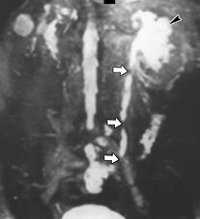

(Слева) КТ с контрастированием, аксиальный срез: на передней стенке живота после частичной колэктомии определяется эллипсовидное скопление жидкости. Визуализируется часть дренирующего чрескожного катетера в центре скопления жидкости; имеются подозрения на инфицирование аспирированного содержимого.

(Справа) КТ с контрастированием этого же пациента в экскреторную фазу, более нижний срез. Обратите внимание на плотное контрастирование мочеточников и на контраст, заполняющий скопление жидкости вокруг катетера.